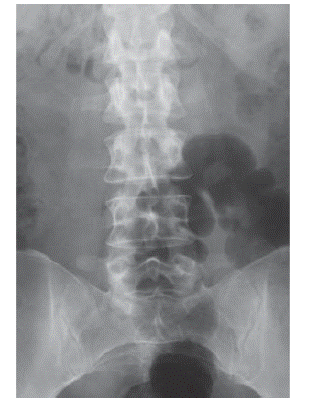

4.10 сурет.Кушинг синдромындағы көкірек және бел омыртқа бөлігінің остеопорозы

4. Остеопороз - науқастардың 90%-да көрініс беретін гиперкортицизмнің ауыр асқынуы. Жиі омыртқа бағанасының көкіректік және бел бөлігі остеопорозбен зақымдалып, компрессиялы сынулар мен омыртқа денесі биіктігінің төмендеуімен сипатталады (4.10 сурет). Рентгенограммада омыртқа денесінің бөлініп шығып тұрған шеткі пластинкалары қасында омыртқа толығымен көрінеді, («шыны тәріздес омыртқа»). Сүйектің сынулары жиі өте қатты ауыру сезімімен және кейде жұлының түбіршіктері жаншылуынан дамитын синдроммен ұштасады. Оның арқа бұлшықеттерінің атрофиясымен бірге қосарласуы жиі сколиоз және кифосколиоз секілді асқынуларға әкеледі. Егер ауру балалық шақта дамыса, баланың өсуі артта қалады, себебі глюкокортикоидтар мөлшерінің артық болуы эпифизарлы шеміршектердің дамуын тежейді.